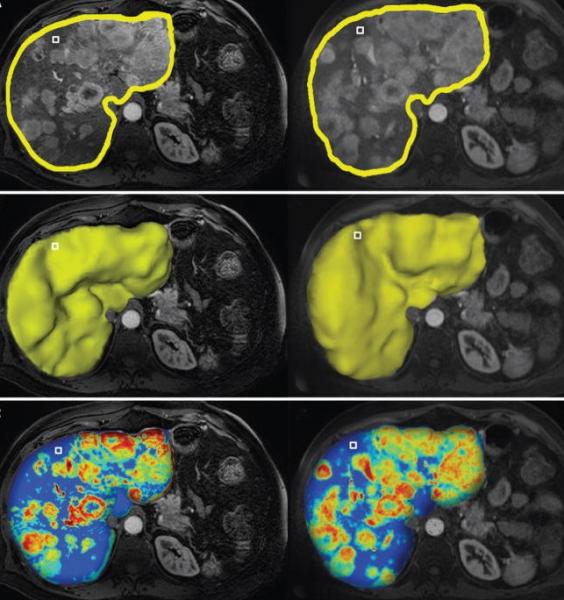

The webinar "Multi-Modality 3D Quantitative Imaging in Cancer Care: Clinical Value and Future Perspectives" focuses on the role of image analysis and artificial intelligence for image-guided, minimally invasive cancer therapies. It introduces the audience to the mechanisms and principles of image analysis, outlines the growing role of machine learning for the therapeutic algorithm and the decision making processes in interventional oncology.

Liver cancer is the second most common cause of cancer-related death worldwide and most cases are diagnosed at intermediate to advanced stages of the disease, making most patients no longer amenable to surgical therapies. Minimally invasive, loco-regional image guided therapies, such as chemoembolization, have become the mainstay therapy for such patients. These image-guided interventions also gave birth to the new field of interventional oncology, a subspecialty of interventional radiology which is increasingly considered as the new and fourth pillar of cancer care (next to medical, surgical and radiation oncology). The explosive growth of such therapies requires new and more efficient intra- and post-procedural imaging solutions. This webinar will focus on the role of image analysis and artificial intelligence for image-guided, minimally invasive cancer therapies and introduce the audience to the mechanisms of action, principles of image analysis and the growing role of machine learning for the therapeutic algorithm and decision making in interventional oncology.

• Review novel software-assisted 3-D quantitative tools to evaluate surrogate endpoints of therapeutic efficacy.